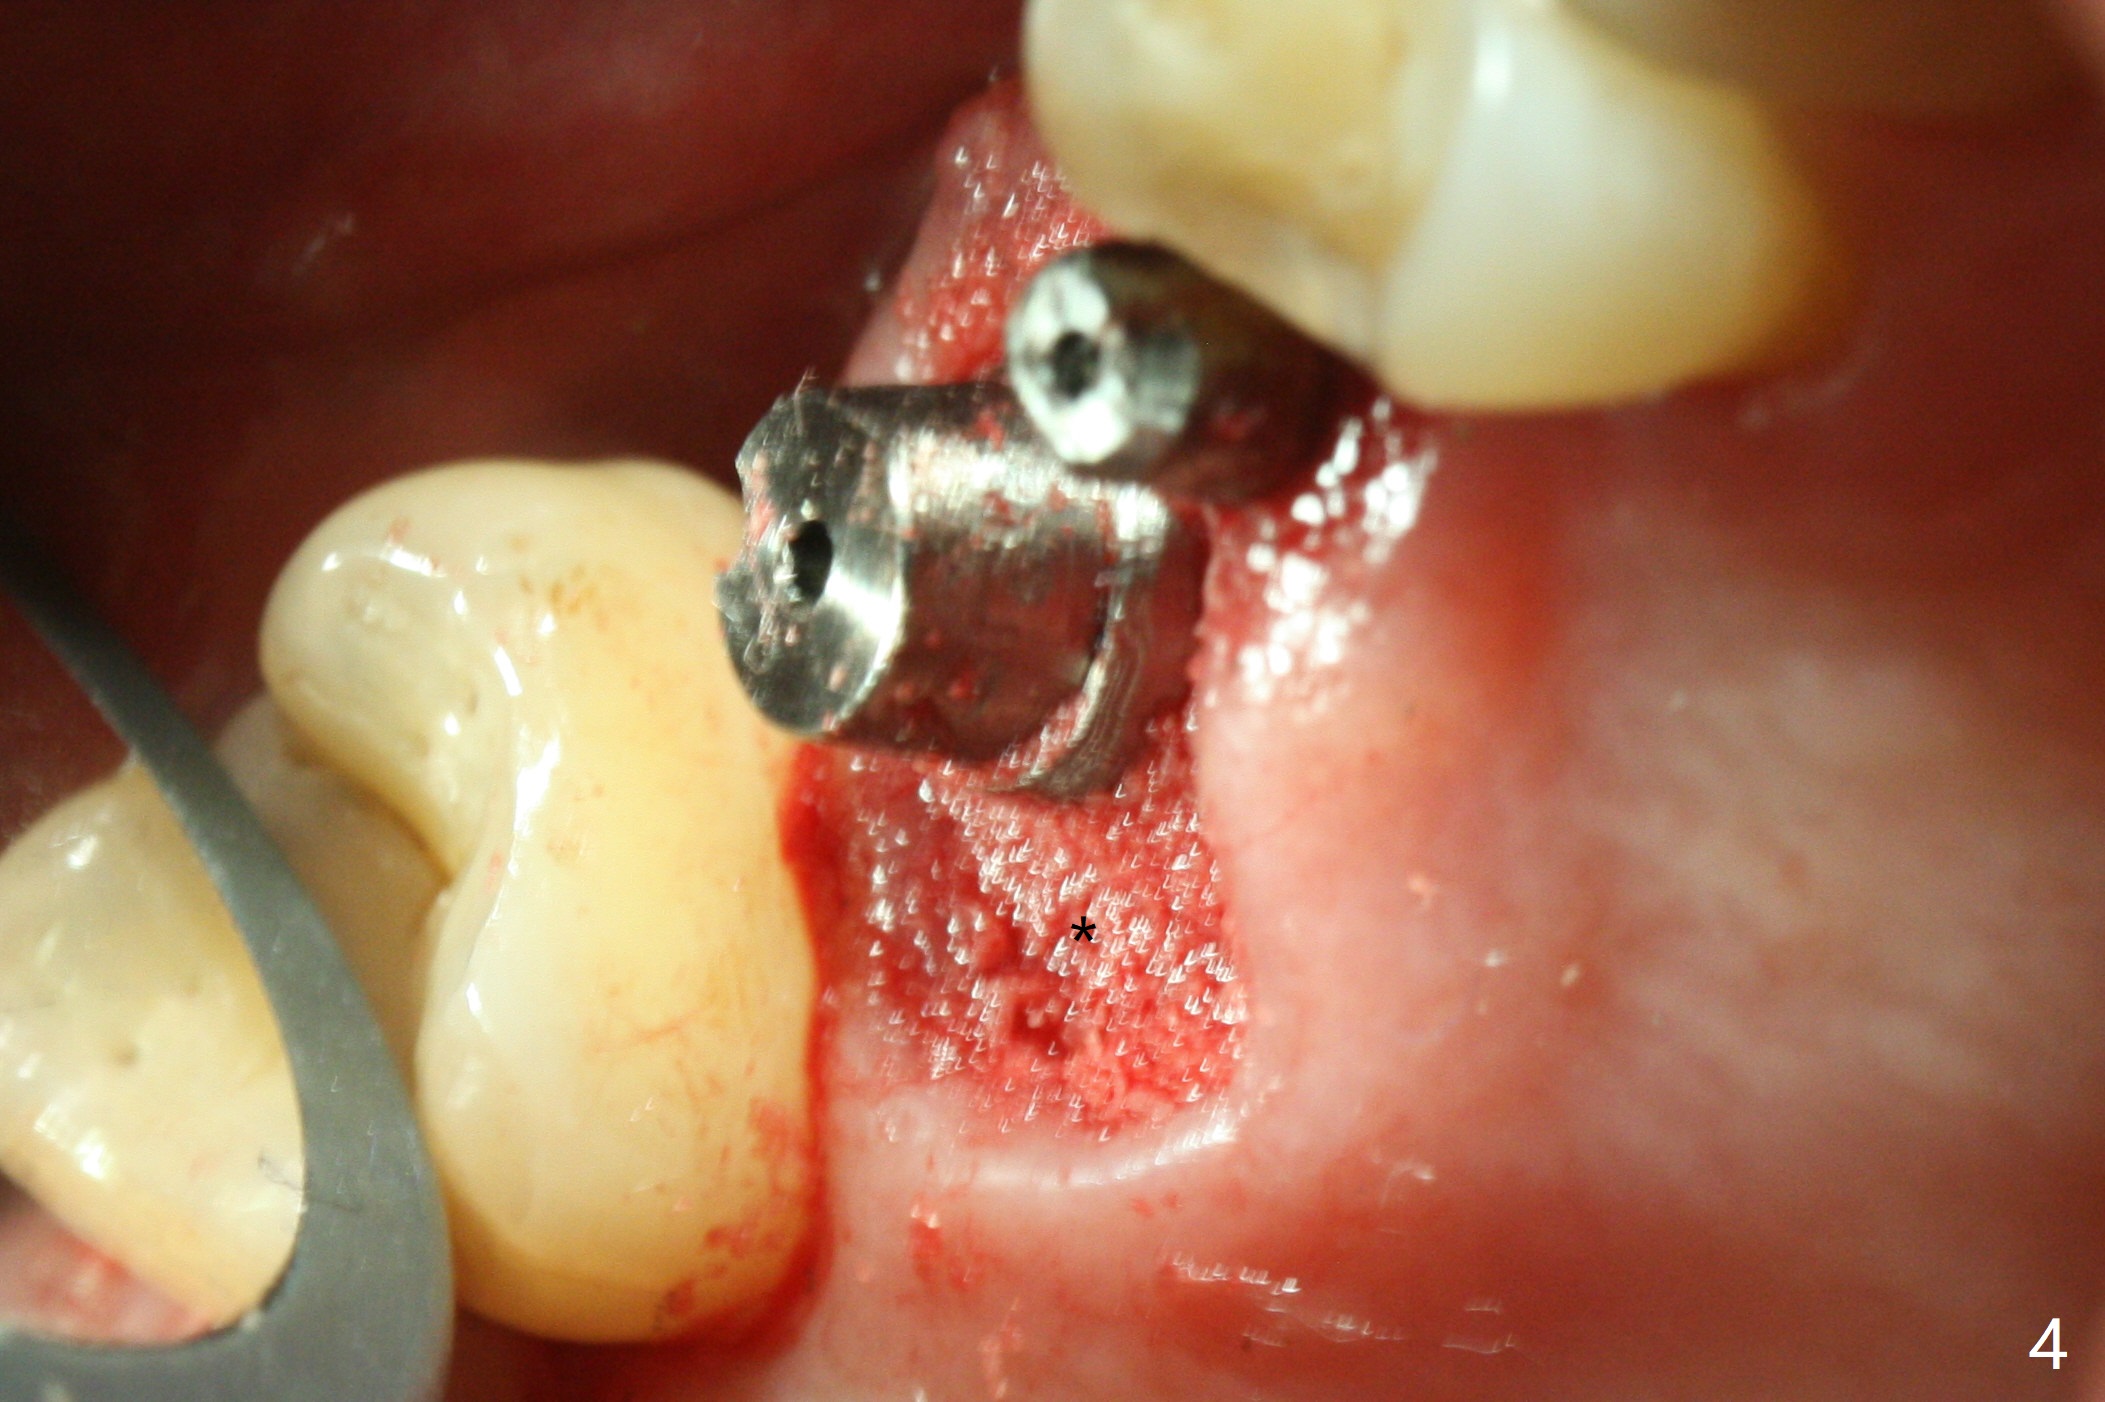

With proper manipulation, a 6x14 mm implant is placed with primary stability (Fig.3). The buccal and palatal socket opening is closed with Vera Graft (allograft, Fig.4 *), which is in turn covered by an immediate splinted provisional. No gap exists 7 months postop (Fig.5,6). Return to Upper Molar Immediate Implant, Prevent Molar Periimplantitis (Protocols, Table), IBS Xin Wei, DDS, PhD, MS 1st edition 09/26/2017, last revision 04/24/2018